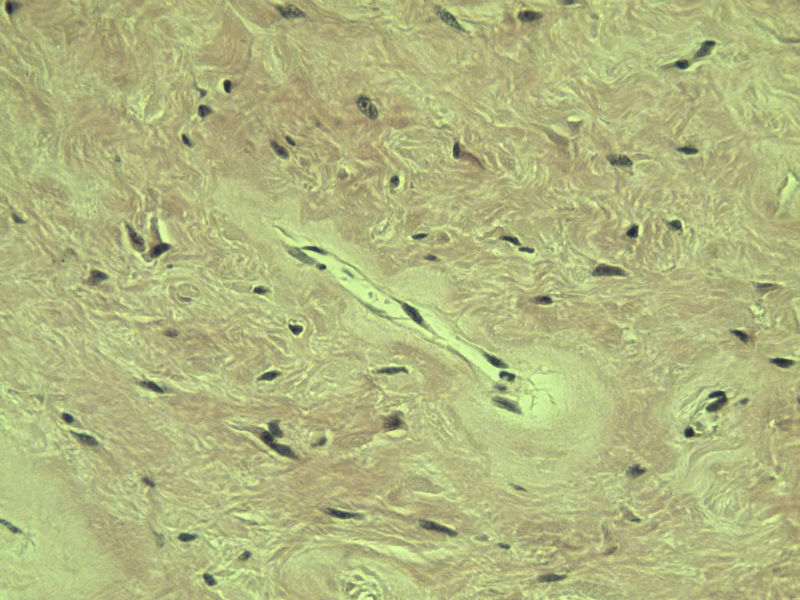

男,51岁, 4月前患者无意中发现右腘窝一包块,约核仁大小无疼痛, 4月来包块进行性生长

灰褐类圆形包块一个,直径 5 cm,切面灰白,实性,编织状。 请各位老师看看 是什么? 谢谢!